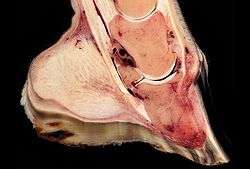

The bones of the hoof are suspended within the axial hooves of ungulates by layers of modified skin cells, known as laminae or lamellae, which act as shock absorbers during locomotion. In horses, there are about 550–600 pairs of primary epidermal laminae, each with 150–200 secondary laminae projection from their surface.[1] These interdigitate with equivalent structures on the surface of the coffin bone (PIII, P3, the third phalanx, pedal bone, or distal phalanx), known as dermal laminae.[2] The secondary laminae contain basal cells which attach via hemidesmosomes to the basement membrane. The basement membrane is then attached to the coffin bone via the connective tissue of the dermis.[1]

Laminitis literally means inflammation of the laminae, and while it remains controversial whether this is the primary mechanism of disease, evidence of inflammation occurs very early in some instances of the disease.[3] A severe inflammatory event is thought to damage the basal epithelial cells, resulting in dysfunction of the hemidesmosomes and subsequent reduction in adherence between the epithelial cells and the basement membrane.[4] Normal forces placed on the hoof are then strong enough to tear the remaining laminae, resulting in a failure of the interdigitation of the epidermal and dermal laminae between the hoof wall and the coffin bone. When severe enough, this results in displacement of the coffin bone within the hoof capsule.[4] Most cases of laminitis occur in both front feet, but laminitis may be seen in all four feet, both hind feet, or in cases of support limb laminitis, in a single foot.[4]

Sinking is less common and much more severe. It results when a significant failure of the interdigitation between the sensitive and insensitive laminae around a significant portion of the hoof occurs. The destruction of the sensitive laminae results in the hoof wall becoming separated from the rest of the hoof, so that it drops within the hoof capsule. Sinking may be symmetrical, i.e., the entire bone moves distally, or asymmetric, where the lateral or medial aspect of the bone displaces distally.[4] Pus may leak out at the white line or at the coronary band. In extreme cases, this event allows the tip to eventually penetrate the sole of the foot. A severe "sinker" usually warrants the gravest prognosis and may, depending upon many factors, including the quality of aftercare, age of the horse, diet and nutrition, skill, and knowledge and ability of the attending veterinarian and farrier(s), lead to euthanasia of the patient.